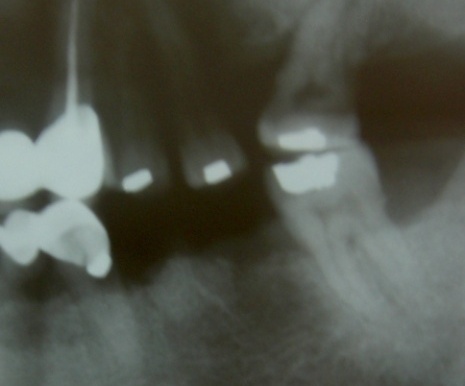

Ejemplo Implantes